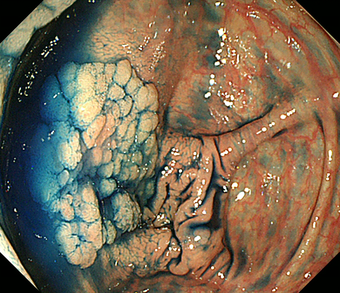

図 大腸がん

大腸がんとは

大腸がんは大腸の壁の最も内側にある粘膜内から発生します。大腸粘膜の細胞のいくつかの遺伝子に変異が生じることが原因と考えられ、発癌を促す遺伝子が現れたり,逆に発癌を抑えている遺伝子が働かなくなったりすることで癌が発生します。大腸がんの発生経路には,ほとんどの場合は良性の大腸ポリープである腺腫が大きくなる過程で癌に進展すると考えられていますが、正常粘膜から直接に癌が発生する経路もあると考えられています。大腸がんの約7割は直腸やS状結腸に発生します 。

大腸癌の肉眼型

大腸癌は見た目の形(肉眼形態)により,0型-4型に分類されています。0型(表在型)は早期がんで、1-4型は進行がんに分類されます。